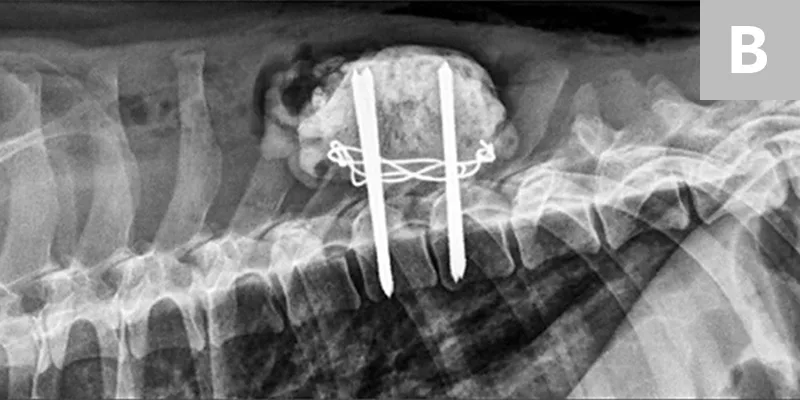

Surgical decompression and stabilization are often recommended for thoracic and lumbar injuries based on the degree of instability and risk for further vertebral column shifting and spinal cord damage. Surgical options include use of positive profile pins or screws with polymethylmethacrylate bone cement, external fixators, and vertebral body plates (Figure 5). Referral to a board-certified neurologist and/or surgeon is recommended for cases in which surgical therapy may be an option. Cats with sacrocaudal luxations may benefit from tail amputation, which removes a source of pain and prevents further traction damage to the sacral nerve roots.

Featured Image

Figure 5

Lateral radiographs taken pre- and postoperatively of a dog after being found in a ditch and presumably hit by a car. (A) There is a T8-T9 subluxation and (inconsequential) T8 spinous process fracture. (B) The subluxation was reduced and stabilized using fully threaded pins, Kirschner wire, and bone cement. The Kirschner wire encircles the pins and is intended to increase the strength of the bone cement. Ideally, these pins would have been placed with more craniocaudal angulation and the construct would have included a third implant spanning the luxation laterally to provide additional support.